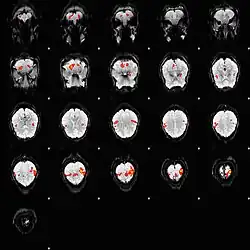

Le signal BOLD (de l'anglais blood-oxygen-level dependent, « dépendant du niveau d'oxygène sanguin ») est le signal qui reflète les variations locales et transitoires de la quantité d'oxygène transporté par l'hémoglobine en fonction de l'activité neuronale du cerveau[1].

L'augmentation de l'activité électrique et métabolique des neurones entraîne un accroissement corrélatif des débits et volumes sanguins régionaux, qui permettent d'apporter aux neurones un supplément d'oxygène et de glucose. Ce couplage neuro-vasculaire requiert des échanges de signaux chimiques (adénosine, monoxyde de carbone, potassium, H+...) et l'intervention des astrocytes, lesquels permettent une vasodilatation locale à l'origine de la réponse hémodynamique. Cependant, cette supplémentation en oxygène via l'oxy-hémoglobine, est très supérieure à ce que le neurone prélève par glycolyse aérobie. En effet, ce mécanisme de production énergétique, qui est déjà mobilisé pour l'entretien des gradients électro-chimiques du neurones au repos, est très vite saturé lors de l'activation de ces mêmes neurones. La production d'énergie est alors transitoirement assurée par une glycolyse anaérobie utilisant le lactate fourni par les astrocytes aux neurones. Il s'ensuit une suroxygénation du sang veineux (le surcroît d'oxygène inutilisé passant des artérioles aux capillaires et veinules) qui modifie localement les propriétés magnétiques des tissus, ce que détecte l'IRM.

L'imagerie par résonance magnétique fonctionnelle repose sur la mesure du signal BOLD.